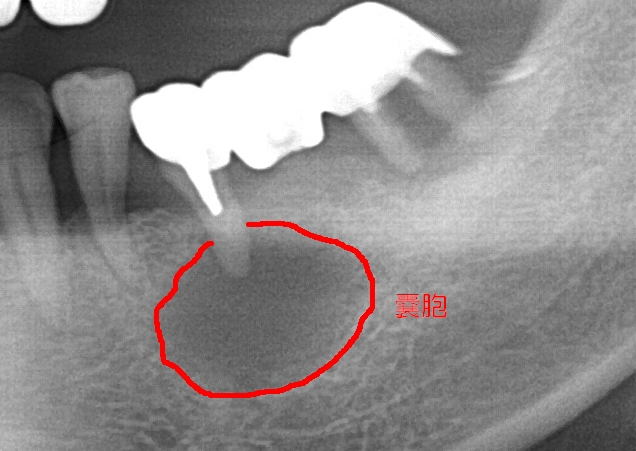

エックス線写真上では、歯根膜空隙とつながる単房性の透過像がみられる。大きなものでは透過像が複数歯に及ぶ場合もある。嚢胞の内容物として黄褐色の粘稠性や漿液性の液体、炎症細胞、剥離上皮細胞、コレステリン結晶が認められる。

確定診断のためには嚢胞壁の確認が重要であるため、臨床診断での確定診断は難しい。

直径10mm以下の小さなものはレントゲンでは歯根肉芽腫と鑑別が困難である。大きなものは他の嚢胞との鑑別を要する。